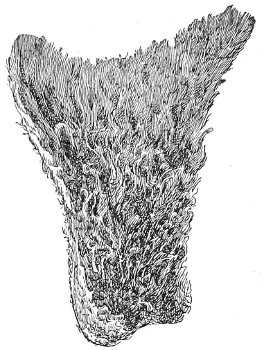

Kraurosis Vulvæ.—Kraurosis vulvæ is a very rare disease, of chronic inflammatory nature, affecting the vulva. The disease is characterized by cutaneous atrophy, with very marked shrinking and contraction of 45 the vaginal orifice. The lesions may be unilateral or circumscribed, but usually the tissues of the labia majora, the nymphæ, and the area surrounding the clitoris and urinary meatus are more or less involved. The cause of the disease has not as yet been determined. It has been observed at every age after puberty, in the nulliparæ as well as the multiparæ, and in the parturient woman. It must be differentiated from pruritus and the atrophic changes which take place after the physiological and induced menopause.

The first symptoms noticed by the patient are usually those of pruritus—an intense itching and burning about the vulva. In some cases the affected tissue early becomes excessively hyperplastic. The mucous membrane and the skin of the vulva are often discolored, small red spots appearing, which are sensitive to touch. Later a peculiar shrinking of the superficial tissue takes place, and the diseased surfaces become dry and whitened. The nymphæ gradually disappear, fusing with the labia majora; and the mucous membrane and skin become shiny and drawn smoothly over the shrunken clitoris. Cracks or fissures appear on the dry surfaces. A sensation of drawing and shrinking of the vulva is now usually experienced. The vaginal orifice gradually narrows and contracts, until frequently the little finger can scarcely be introduced. When this last condition of atrophy is reached, the pathological process is arrested, the subjective sensations of shrinking pass away, and the symptoms resembling pruritus are no longer experienced. The shrunken and contracted vaginal orifice, however, persists and is never spontaneously restored.